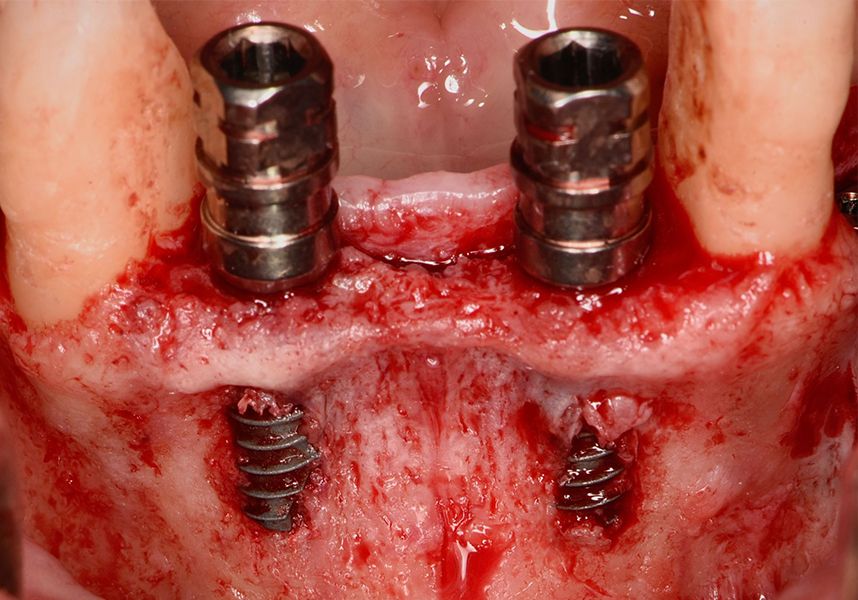

Respecting the three-dimensionally correct position of the implant led to bone fenestration, leaving the apical part of the apex of the implant exposed almost to the mid-point of its length at 42 and a third in 32.

To treat the defect, bone regeneration was carried out simultaneous to the surgical process, with an autologous bone graft from the patient. In the internal part of the graft we used autologous cortical bone obtained by scraping (Safescraper) and from the biological drilling, at low revolutions and without irrigation, from the other implant beds. In the external layer of the regeneration we used a xenograft (Genoss, Osteogenos) and this was covered with a reabsorbable collagen barrier membrane (Evolution STD, Osteogenos).

In the posterior sector three Biomimetic Ocean IC implants of 4.0x10 were inserted in positions 36, 34 and 46 with delayed load. A small regeneration was also carried out with autologous bone in the implant in position 34, where there was no exposure, but the vestibular cortical was very fine after implant insertion.